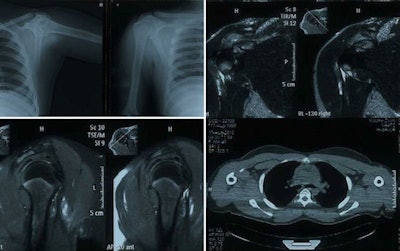

Radiographs were performed either on a digital radiography (DR) system or a computed radiography (CR) system. Image processing or enhancement was applied on DR images and CR images depending on requirement.

Ultrasound was performed using a 5- to 13-MHz linear probe, but in large patients a lower frequency probe of 2 MHz to 6 MHz was necessary. CT was done on a four-slice spiral scanner, and MRI was performed in sagittal, coronal, and axial planes. In all patients, T1- and T2-weighted images were obtained. In addition, T1-weighted gradient-recalled echo (GRE), T2-weighted fast spin-echo (FSE), T2-weighted fat-suppressed, and other sequences, such as proton density-weighted and proton density-weighted fat-suppressed, were done as and when required.

All investigations were performed by a radiologist with 11 years of experience as a general radiologist and one year as a musculoskeletal radiologist. Radiographs were performed in cases of suspected fractures, followed by a CT scan if the diagnosis was in doubt. Ultrasound was performed in all cases of suspected soft-tissue injuries, followed by MRI for further characterization in cases of clinical indication. CT also was performed in cases of suspected osseous injury.